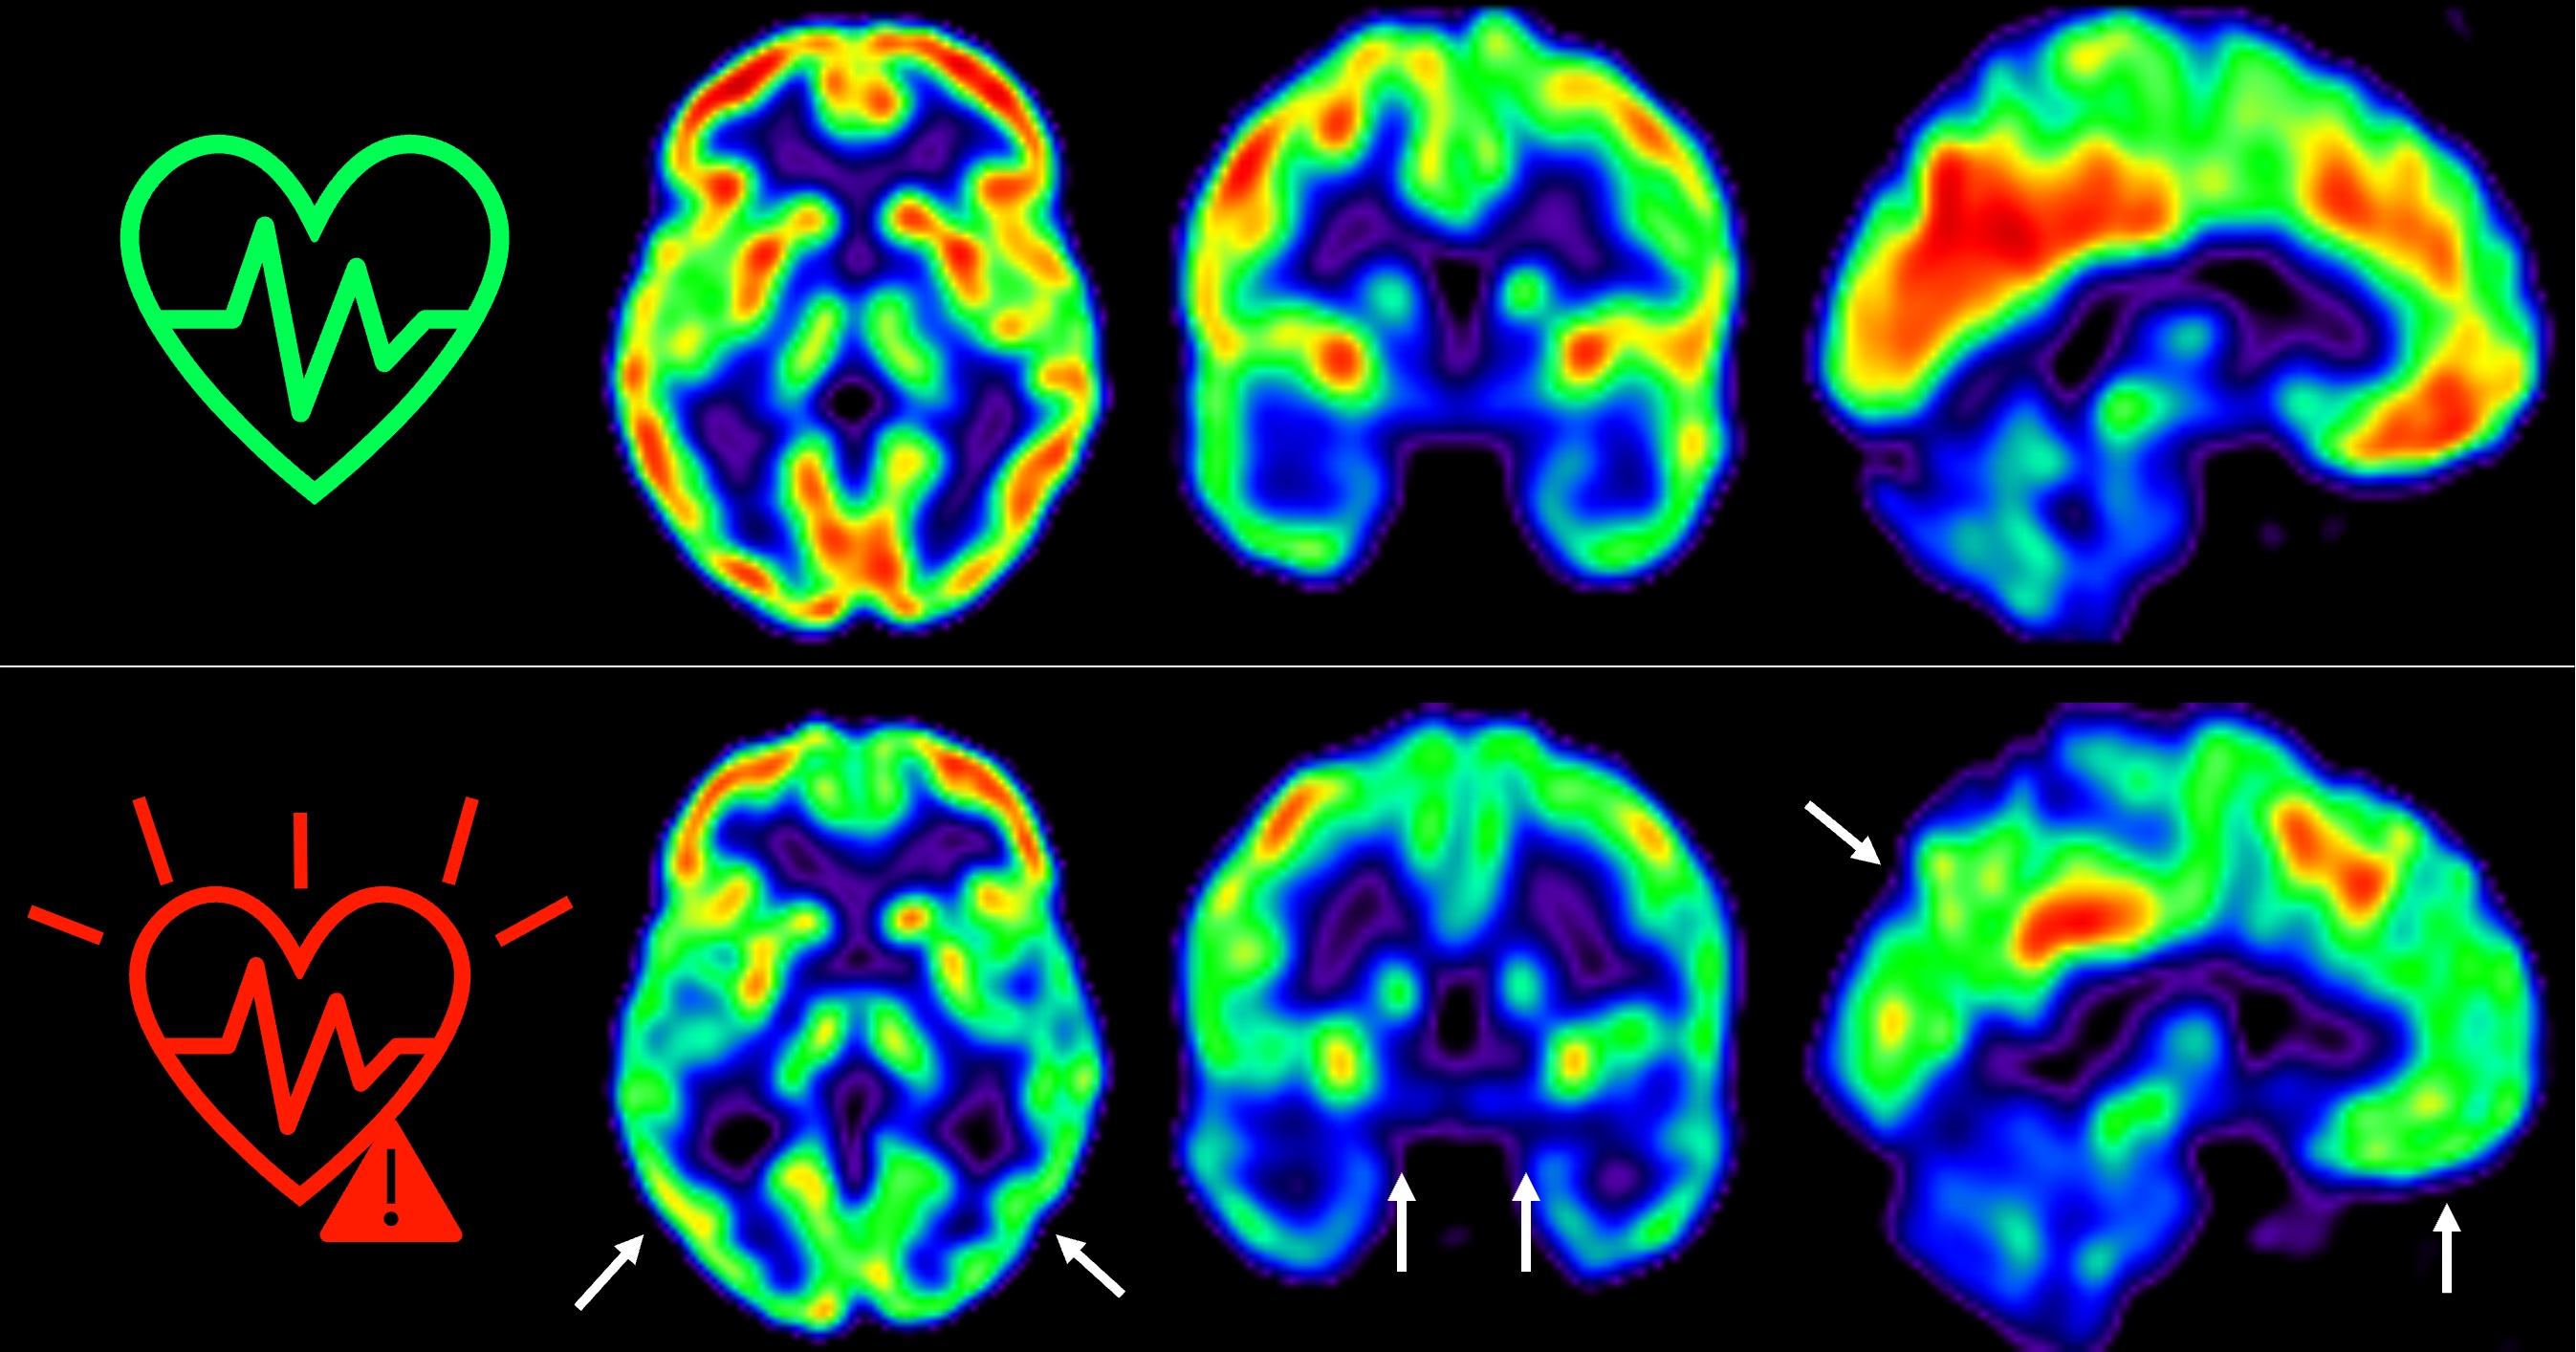

Demuestran que el envejecimiento prematuro en personas con VIH lo causa la misma infección y no solo el tratamiento con antiretrovirales